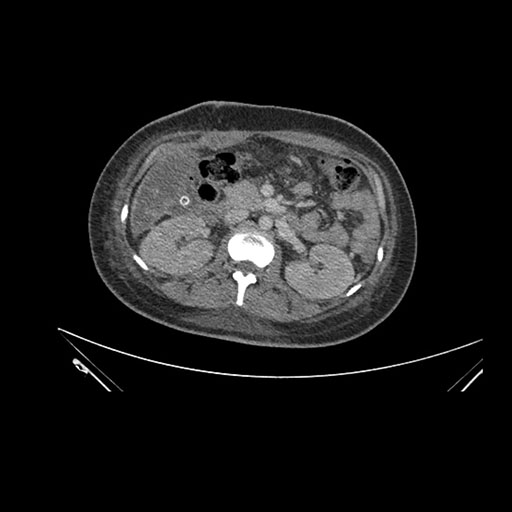

Axial Arterial

Imaging analysis

Based on initial findings, which issue(s) would you be most concerned about?